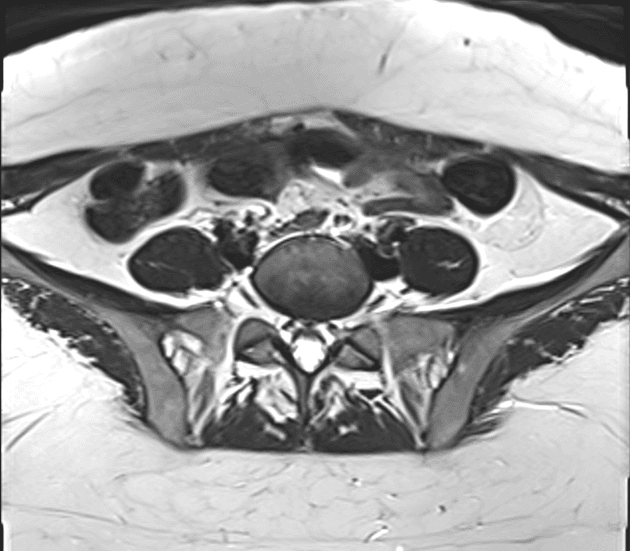

Axial C+ portal venous phase

Phần thấp của cơ thẳng bụng phải (right rectus abdominis muscle) cho thấy một tổn thương tăng quang không đều, chủ yếu dạng đặc (mainly solid), kích thước 5,3 x 4,4 x 4,1 cm, liên quan đến sẹo mổ lấy thai trước đó.

Siêu âm tổn thương cho thấy tổn thương giới hạn không rõ (ill-defined), hình dạng không đều (irregular), không đồng nhất (heterogenous), giảm âm (hypoechoic) và có một số mạch máu bên trong (some vascularity within).

Với tiền sử điển hình ở bệnh nhân này, tổn thương thành bụng phải vùng hạ vị phù hợp với (compatible with) chẩn đoán lạc nội mạc tử cung ở thành bụng liên quan đến sẹo mổ lấy thai.

- "Đặc điểm hình ảnh bao gồm tổn thương mô mềm tăng quang không đều, ranh giới không rõ, giảm âm, dị dạng và có mạch máu bên trong trên siêu âm và cộng hưởng từ."